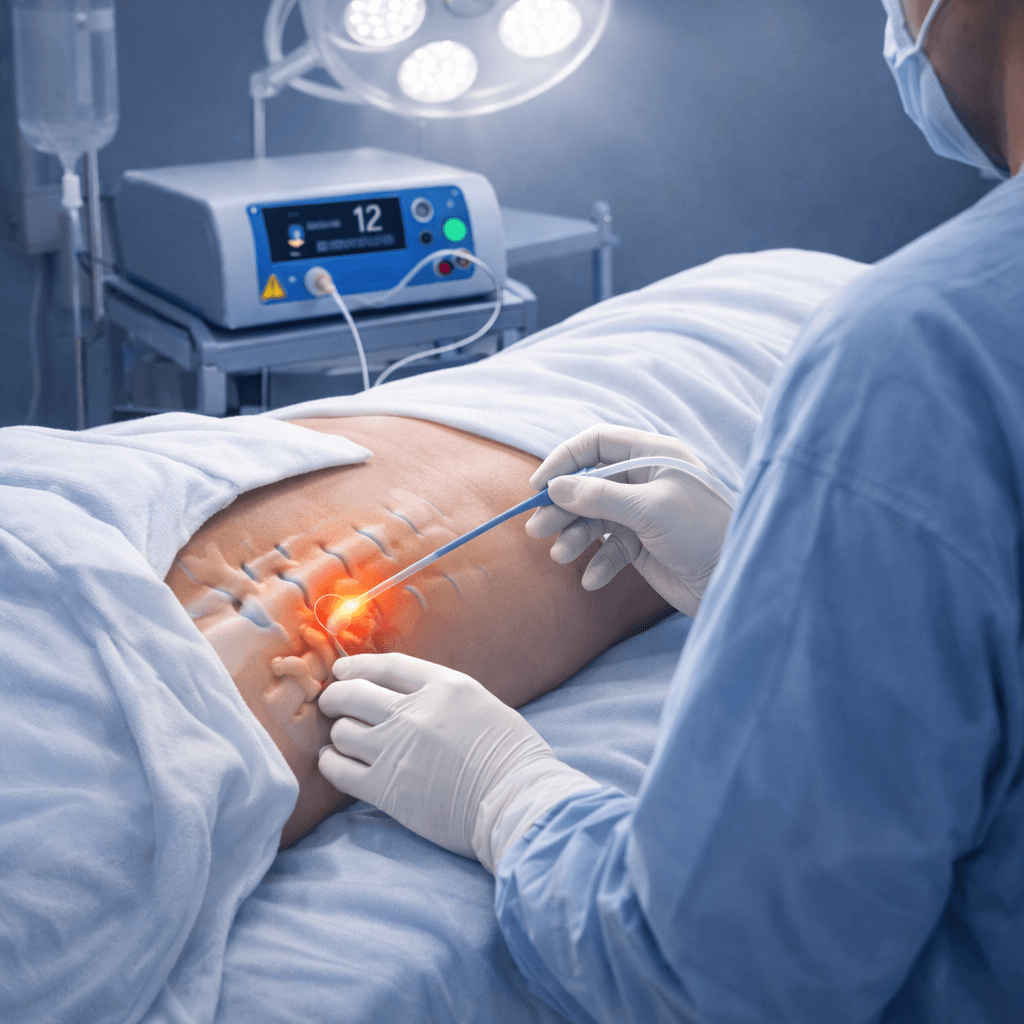

Robust Medical Diode Lasers, Fibres and Staplers

Our Product Applications

Minimally invasive procedures across multiple surgical specialities